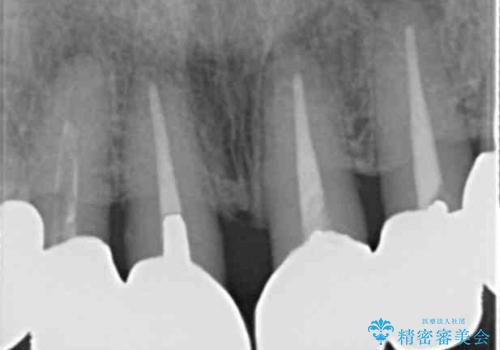

- 前歯のセラミック治療から4年半経過した患者様です。

4年ぶりに来院して下さいました。

患者様の良好なセルフケアと精密な適合の良いクラウンにより、歯肉の腫脹や退縮も認められませんでした。